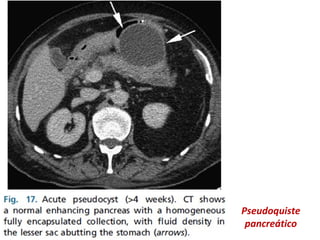

PSEUDOQUISTE PANCREATICO:

•Una APFC puede gradualmente pasar hacia un

pseudoquiste, después de 4 semanas.

•Ocurre como complicación de la pancreatitis

aguda en 10-20%.

•Colección de líquido peripancreático bien

delimitada, redondas u ovales, homogénea y de

baja atenuación.